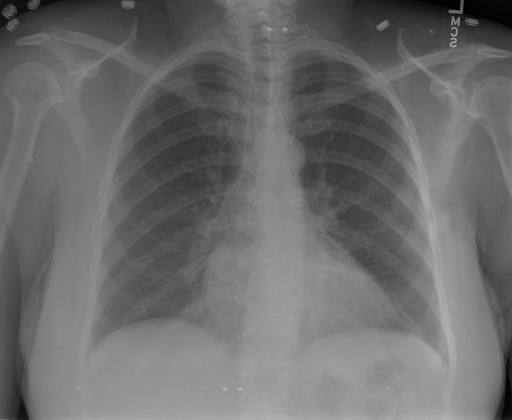

- (1)准备[诊疗报告(中文)](./data/Xray/openi-zh.json)和[X光影像](https://pan.baidu.com/s/13GBsDMKf6xBZBSHpoWH_EA?pwd=k9sh)在`data/Xray`文件夹下; - (2)开始训练: ```bash # 设置CUDA变量,主要是为了解决有时候直接训练而出现无法正确加载到显卡问题 export CUDA_VISIBLE_DEVICES=0,1,2,3 # 开始训练 bash finetune_XrayGLM.sh ``` 这里的复现过程非常简单,主要是很多过程我们都为大家准备好了,大家可以随时复现一个自己的`XrayGLM`。 ### 4.模型训练(通用) ## 效果展示 影像诊断: |X光影像|诊疗报告(医生)|XrayGLM| |:-|:-|:-| |![](./data/Xray/2_1.png)|根据X射线图像,心脏大小正常,肺部看起来很清晰。已经排除了肺炎、积液、水肿、气胸、腺病、结节或肿块的存在。该发现表明一切正常。换句话说,总体印象是胸部正常。|X光片显示,心脏大小正常。肺部没有气胸或胸腔积液的证据。骨骼结构看起来没有任何异常。总的来说,X光片表明没有发现急性心肺疾病的迹象。| |![](./data/Xray/2882_1.png)|X光图片显示没有扭曲的区域、可疑的骨质不透明度或胸腺积液。心脏大小轻微增大,但非常稳定。此外,没有气胸的证据,肺野也正常。总体来说,X光片显示没有急性心脏异常,但要注意轻微的心脏扩大。|X光片显示,心脏大小正常。肺部和纵隔轮廓清晰,没有气胸或胸腔积液的证据。骨骼结构完整,没有任何急性异常。| |![](./data/Xray/2577_1.png)|心影形态在正常范围内。没有急性骨质异常。有可能出现没有明显的吸水或肺实质状况的线索。没有大面积积液或气胸。有可能怀疑其有误吸或肺实质问题。为了确诊和治疗,可能需要进行适当的影像学随访。|心脏大小正常,肺部和纵隔轮廓清晰。没有急性异常或活动受限的证据。没有任何明显的气胸、胸腔积液或肺不张的迹象。此外,也没有发现任何局灶性骨质异常或其他急性疾病。| 多轮对话: |X光影像|诊疗报告(医生)| |:-|:-| |![](./data/Xray/861_1.png)|右侧主动脉突出观察到。心脏大小正常。胸部未发现明显的肺气肿、胸膜积液或可疑的肺部病变。报告指出已知右侧主动脉情况正常。| ```bash >> X光影像路径:./data/Xray/861_1.png >> 用户:这是一张什么图? >> XrayGLM:这张图片显示的是一张肺部检查的X光片。 >> 用户:请描述这张胸部X光片的诊断结果 >> XrayGLM:心脏大小正常,肺部清晰。没有急性心肺疾病的证据。 >> 用户:是否存在肺气肿? >> XrayGLM:没有肺气肿。心脏大小正常,肺部清晰。没有发现急性心肺疾病的证据。 >> 用户:平时饮食该注意什么? >> XrayGLM:饮食应该健康,均衡。建议增加蛋白质的摄入量,因为蛋白质有助于维持肌肉和骨骼的健康。多食用蔬菜、水果、全谷物以及健康的脂肪来源如橄榄油、鱼类等可以帮助获得足够的维生素和矿物质。此外,避免过度饮酒或吸烟,这些习惯可能会对心脏健康产生负面影响。 ``` ## 未来展望 1. 模型的能力更多来源于数据的支持,`OpenI-zh`作为微调数据集,其数据量足以支持研究,在更广泛的任务和性能表现上,我们认为**在大规模数据集上预训练并在高质量少量数据集上微调是一种可行的方案**; 2. 普遍意义的理解上,视觉多模态模型=视觉模型+语言模型。除了需要关注视觉模型信息与语言模型输出的搭配外,还需要**额外关注到语言模型的加强,在人机的对话中,尤其是医疗语言模型的问答上,除了专业的医疗问题回答,带有人文情怀的有温度的回答更应该是我们追寻的目标**。 ## 项目致谢 1. [VisualGLM-6B](https://github.com/THUDM/VisualGLM-6B)为我们提供了基础的代码参考和实现; 2. [MiniGPT-4](https://github.com/Vision-CAIR/MiniGPT-4)为我们这个项目提供了研发思路; 3. ChatGPT生成了高质量的中文版X光检查报告以支持XrayGLM训练; 4. [gpt_academic](https://github.com/binary-husky/gpt_academic)为文档翻译提供了多线程加速; 5. [MedCLIP](https://github.com/RyanWangZf/MedCLIP) 、[BLIP2](https://huggingface.co/docs/transformers/main/model_doc/blip-2) 、[XrayGPT](https://github.com/mbzuai-oryx/XrayGPT) 等工作也有重大的参考意义; ![](./assets/images/mpu.png) 这项工作由[澳门理工大学应用科学学院](https://www.mpu.edu.mo/esca/zh/index.php)硕士生[王荣胜](https://github.com/WangRongsheng) 、[段耀菲](https://github.com/IsBaSO4) 、[李俊蓉](https://github.com/lijunrong0815)完成,指导老师为檀韬副教授、[彭祥佑](http://www.patrickpang.net/)老师。 *特别鸣谢:[USTC-PhD Yongle Luo](https://github.com/kaixindelele) 提供了有3000美金的OpenAI账号,帮助我们完成大量的X光报告翻译工作 ## 免责声明 本项目相关资源仅供学术研究之用,严禁用于商业用途。使用涉及第三方代码的部分时,请严格遵循相应的开源协议。模型生成的内容受模型计算、随机性和量化精度损失等因素影响,本项目无法对其准确性作出保证。即使本项目模型输出符合医学事实,也不能被用作实际医学诊断的依据。对于模型输出的任何内容,本项目不承担任何法律责任,亦不对因使用相关资源和输出结果而可能产生的任何损失承担责任。 ## 项目引用 如果你使用了本项目的模型,数据或者代码,请声明引用: ```bash @misc{wang2023XrayGLM, title={XrayGLM: The first Chinese Medical Multimodal Model that Chest Radiographs Summarization}, author={Rongsheng Wang, Yaofei Duan, Junrong Li, Patrick Pang and Tao Tan}, year={2023}, publisher = {GitHub}, journal = {GitHub repository}, howpublished = {\url{https://github.com/WangRongsheng/XrayGLM}}, } ``` ## 使用许可 此存储库遵循[CC BY-NC-SA](https://creativecommons.org/licenses/by-nc-sa/4.0/) ,请参阅许可条款。